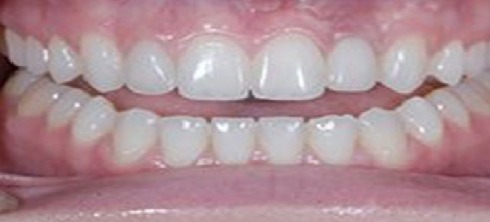

A 26-year-old female with severe crowding. Comprehensive orthodontic treatment was completed. Patients were amazed by the results.

Crowding and constricted arch. Comprehensive orthodontic treatment was performed, and teeth alignment was restored.